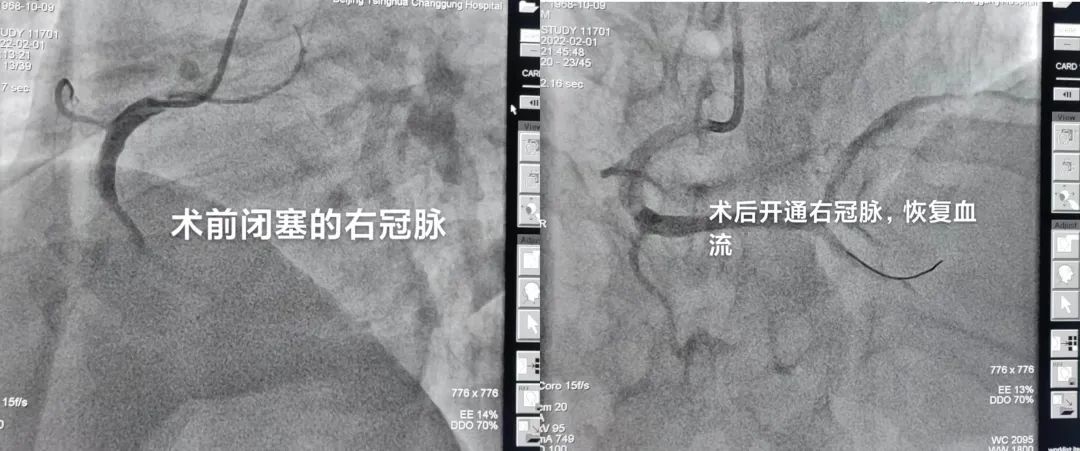

接诊的宋开元医生立马完成心电图检查,明确诊断为急性右室下壁心肌梗死。时间就是生命,时间就是心肌。然而患者此时没有直系亲属,行政总值班果断签字抢救,立刻启动胸痛中心急性心肌梗死救治“绿色通道”!内科二线高博医生,心脏内科三线佘飞医师已经同时赶到急诊参与救治,与此同时通知心脏介入备班医师薛亚军、耿雨到位。患者完成核酸检测及肺部CT后,导管室已一切准备完毕,患者直接转入进行介入手术。术中医生从梗塞的右冠脉内抽取出大量血栓,冠脉恢复血流再灌注,患者转危为安,返回心脏重症监护室。从接诊赵大叔到冠脉血管开通,不到60分钟。